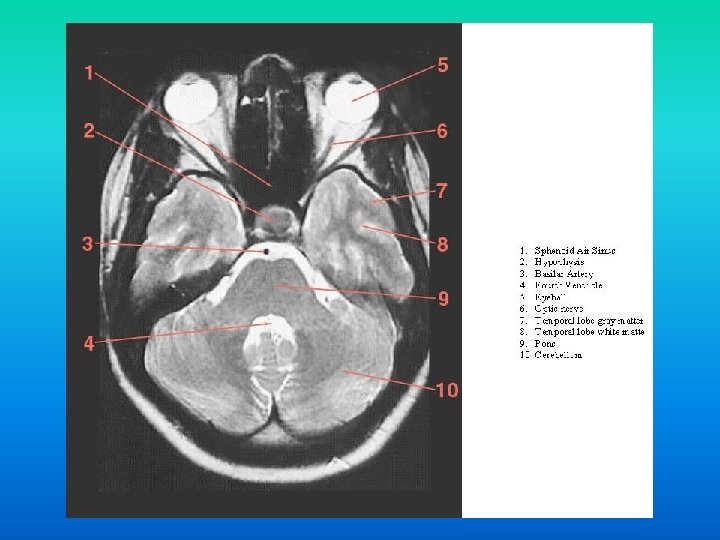

Secventa scurta T 1 Secventa lunga T 2, DP § contrast anatomic § (s. a. alba, s. c. gri, LCR negru) § leziune = hiposemnal § grasime, met. Hb, melanina = Hsemnal § contrast invers § (LCR > s. c. > s. a. ) § leziune = hipersemnal § lichide = hipersemnal

n Patologiile localizate in regiunea sella turcica ocupa un rol aparte in patologiile intracraniene din cauza structurilor de importanta vitala situate in regiune: • Hipofiza. Arterele carotide (si implicit inelul arterial al creerului). Sinusul cavernos (+ nervii cranieni). Chiasma optica (0. 5 cm supraselar). • • •